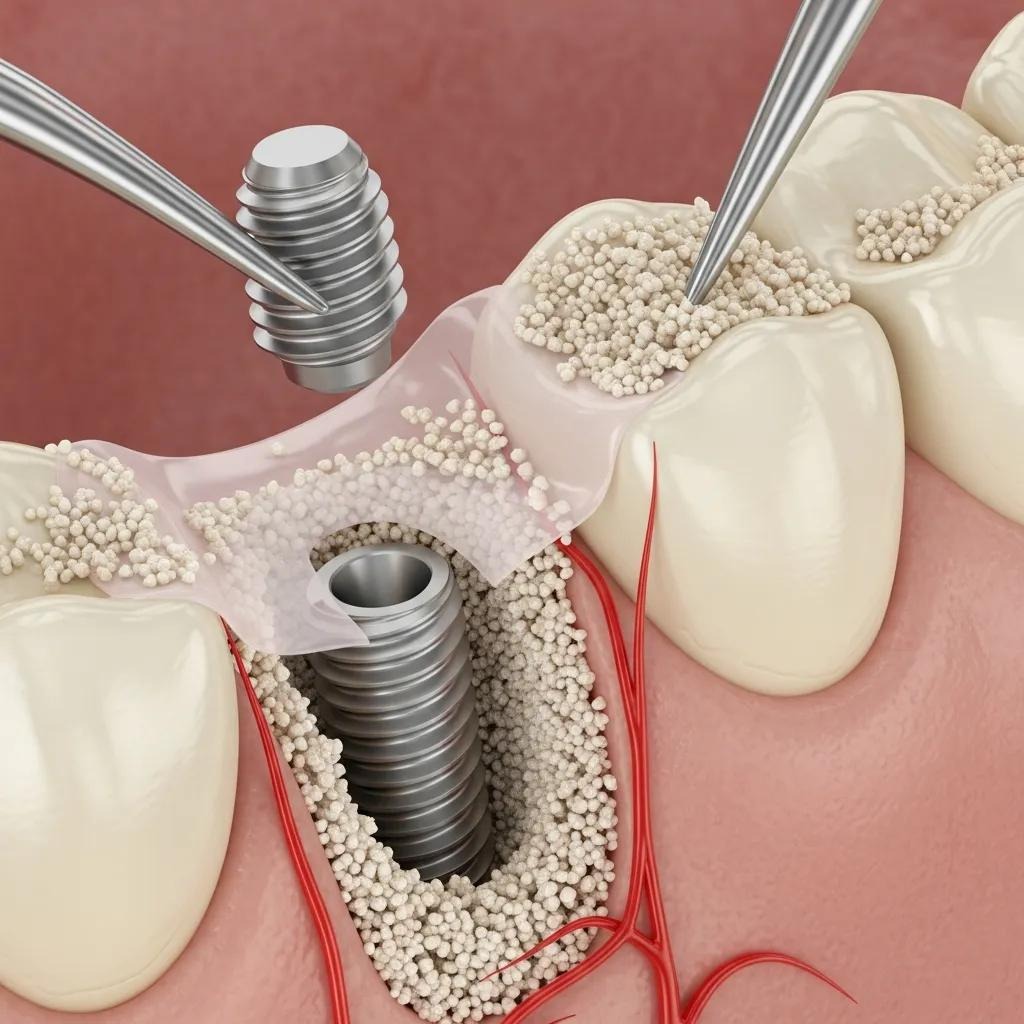

Bone grafting is a surgical procedure that places bone tissue into areas of deficiency to restore jaw volume and contour. For dental implants, grafting rebuilds structural support so an implant can be anchored predictably, which directly improves stability.

In cases of jawbone loss, insufficient bone can complicate implant placement. Grafting addresses these deficits and supports integration between the implant and native bone, which is critical for durable restorative outcomes.

Bone quality, volume, height and width critically influence implant stability, success and survival. When bone is inadequate, various grafting procedures can be used to restore volume. The choice of graft material depends on factors such as the amount of bone required, implant site, patient preference and clinician assessment. Supplemental bone may be sourced from autogenous, allogeneic or xenograft origins, and materials are presented in different formulations, including particulate grafts and bone blocks.

Augmenting the jaw with graft material provides the structural support required for implants to osseointegrate — the biological fusion of implant and bone — which underpins implant stability and longevity.

Patients who receive grafts commonly achieve improved implant anchorage and long-term success; grafting also contributes to the restoration and health of the jawbone.

- Demineralized Bone Matrix (DBM) : A processed form of allograft that retains natural growth factors to support bone regeneration.

- Calcium Phosphate Ceramics : Synthetic materials that encourage bone formation and integrate with the jawbone.

- Collagen Membranes : Used with graft materials to support healing and prevent soft tissue ingrowth.

Technique selection is based on the patient’s clinical needs, ranging from minimally invasive approaches to more extensive surgical procedures. Choosing appropriate materials and methods is essential for reliable outcomes.